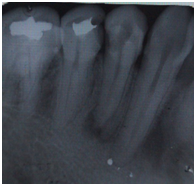

A 35‑year‑old female patient walked into our clinic with the chief complaint of severe pain in the lower jaw right posterior region since 2 days. Oral examination revealed occlusal caries in the lower right mandibular first premolar and secondary caries in second premolar. The tooth was sensitive to percussion and showed an exaggerated response on cold and electric pulp testing. Radiological findings showed coronal radiolucency involving pulp, widening of periodontal ligament (PDL) space, large pulp chamber without any constriction at cementoenamel junction, the condition was diagnosed as acute irreversible pulpitis with apical periodontitis in both the premolars (Figure 1) Cone-beam computed tomography (CBCT) was carried out for confirming numbers of roots and canals of mandibular right second premolar. The CBCT images were taken out using three‑dimensional (3D) Accuitomo scanner (J. Morita, Kyoto, Japan), with Viewer Plus software (J. Morita), which produced a smallest field of view images, to reduce the radiation dosage. A three canals were found, two buccally and one lingually (Figure 2). A non‑surgical root canal treatment was planned accordingly. The patient received local anesthesia with 2% lidocaine and 1:100,000 epinephrine and the rubber dam placement. Following the removal of old filling, careful examination of the pulpal floor revealed three separate mesiobuccal, distobuccal and lingual orifices. The access cavity outline was modified into triangular shape to establish straight‑line access for all root canals. The working length was established using Root ZX II (J. Morita, Tokyo, Japan) and confirmed radiographically (Figure 3). Instrumentation is achieved with Hero Shaper (Micro Mega) to size 30 4%, copious irrigation with 2.5% NaOCl and 17% EDTA was carried out during the instrumentation phase. All canals were dried with sterile paper points and then filling using matching gutta‑percha cones and AH‑plus sealer (Dentsply Maillefer, Ballaigues, Switzerland) until canal orifices (Figure 4) Postendodontic restoration was done followed by tooth preparation and Zirconia‑based full coverage crown cementation. Fifteen months follow‑up radiograph revealed satisfactory healing and healthy status of periapical tissues (Figure 5).

Figure 1 Pre-operative.